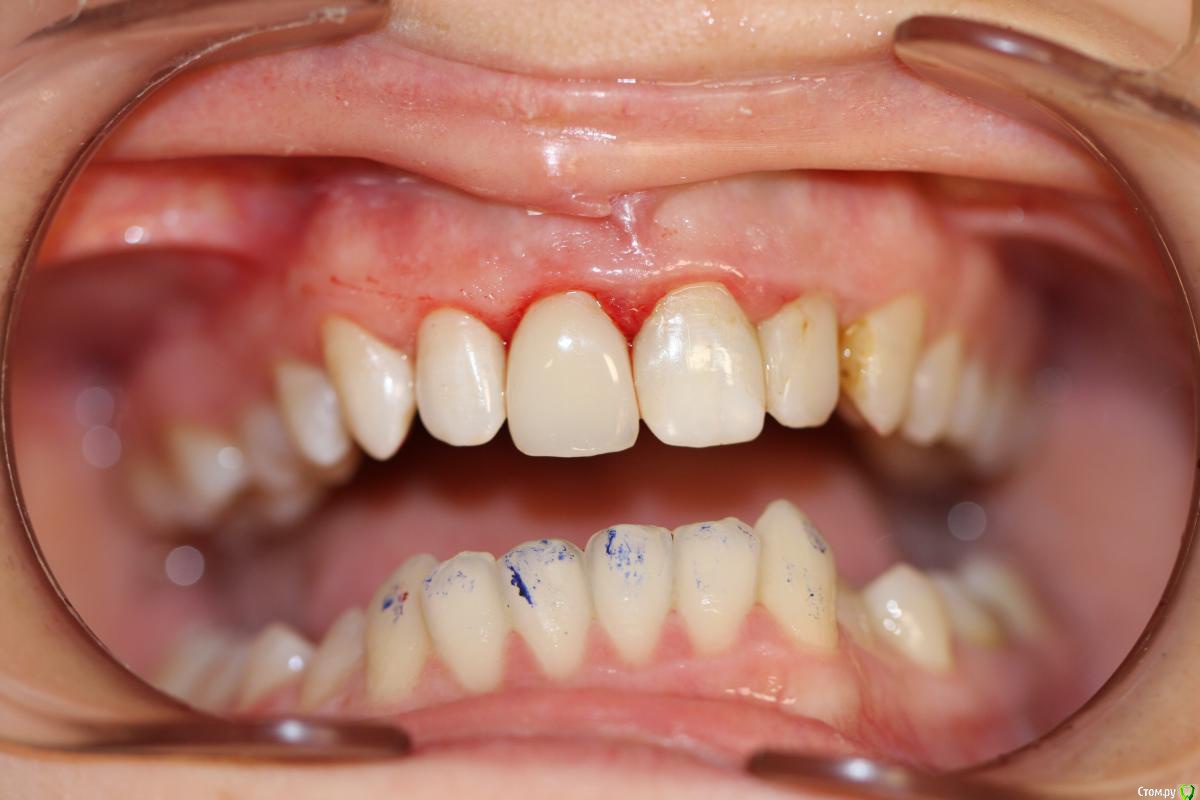

skeettrap Опубликовано 19 марта, 2016 Поделиться Опубликовано 19 марта, 2016 Работа из категории - для души. Попутно сделан кариес у 12 с медиальной стенки , 21 - только подполирована медиальная стенка. 3 Ссылка на комментарий

krokomot Опубликовано 19 марта, 2016 Поделиться Опубликовано 19 марта, 2016 Для бюджета, очень даже не плохо, учитывая общую ситуацию во рту. В посте не хватает кадрирования фотографий ( выровнять, обрезать), ну конечно рентгеновского снимка. Ссылка на комментарий

skeettrap Опубликовано 20 марта, 2016 Автор Поделиться Опубликовано 20 марта, 2016 Для бюджета, очень даже не плохо, учитывая общую ситуацию во рту. В посте не хватает кадрирования фотографий ( выровнять, обрезать), ну конечно рентгеновского снимка.Спасибо за отзыв. Фотограф я начинающий. Буду стараться.По поводу сломаться - скорее сломает 21,22 (мертвые), если не появится больше. Этот остался в яблоке.Про эстетику: 21,22 с серым оттенком, 12 - А2 .МК будет выделяться. Емах понятно лучше на 11,21,22 с соответствующей подготовкой,но ей это не потянуть.А так , по-моему, хорошее решение с возможностью улучшения в любой момент. Ссылка на комментарий

Доктор Дмитрий Опубликовано 20 марта, 2016 Поделиться Опубликовано 20 марта, 2016 Сомнительная работа с точки зрения функции, зубы разные по форме и по цвету немного тоже. Ссылка на комментарий

skeettrap Опубликовано 20 марта, 2016 Автор Поделиться Опубликовано 20 марта, 2016 А штифт из канала достать, то еще удовольствие Вааще не проблема. Кстати, я не встречал переломов СВШ(стаж 20 лет). Бывало доставал расфиксированные частично, когда доктора пытались фиксировать на текучий.Сомнительная работа с точки зрения функции, зубы разные по форме и по цвету немного тоже.Если придет - сфоткаю когда влагу наберут соседние. По форме - не стал скруглять медиальный край, как у 21, лучше добавить у 21(мне так кажется). Ссылка на комментарий

anvladd Опубликовано 21 марта, 2016 Поделиться Опубликовано 21 марта, 2016 зубы разные по форме и по цвету немного тоже.Форма норм а цвет разный потому что пересохли зубы за время реставрации,через пару дней одинаково будет. Ссылка на комментарий